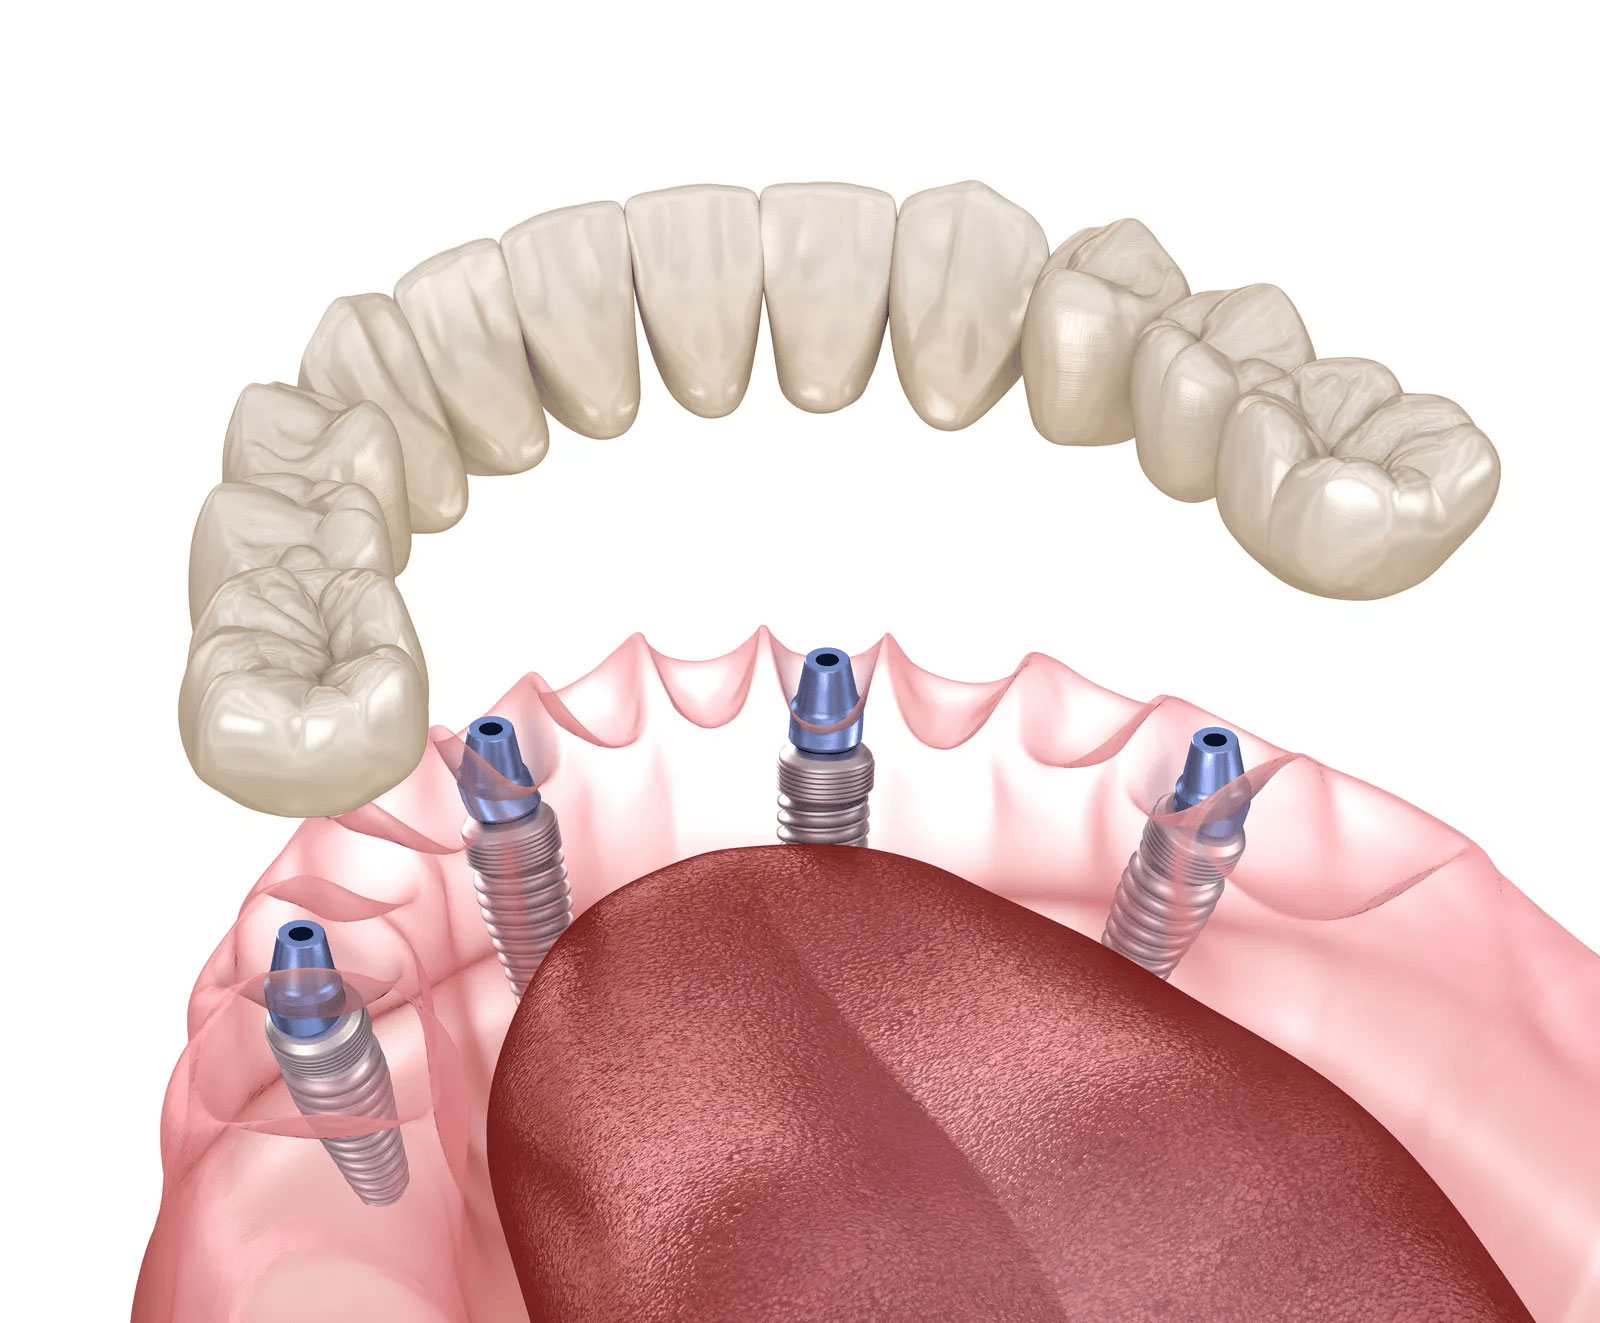

All-on-4とは、片顎につき最低4本のインプラントで、すべての歯を支える治療法です。必要なインプラントの本数を抑えながら、多くの歯を安定して支えることができます。

All-on-4は、少ない本数でお口全体を支える設計のため、身体的負担・治療期間・費用のバランスを考慮しながら、しっかり噛める状態を目指せる点が大きな特長です。

All-on-4では、骨が比較的しっかり残っている場所を選び、インプラントを斜めに埋入します。そのため、一般的なインプラント治療に比べて、必要とされる骨量を抑えやすい治療法です。